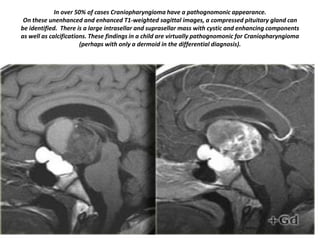

In over 50% of cases Craniopharyngioma have a pathognomonic appearance.

On these unenhanced and enhanced T1-weighted sagittal images, a compressed pituitary gland can

be identified. There is a large intrasellar and suprasellar mass with cystic and enhancing components

as well as calcifications. These findings in a child are virtually pathognomonic for Craniopharyngioma

(perhaps with only a dermoid in the differential diagnosis).